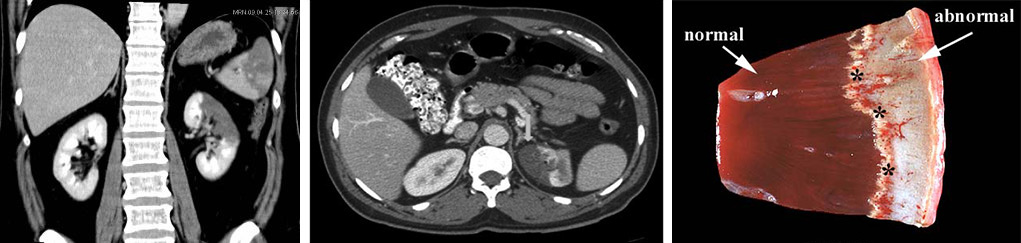

Характеристика кровотока в органе (магистральный тип) влияет на внешний вид инфаркта почки. Обычно он имеет клиновидную форму светлого цвета, иногда с венчиком кровоизлияний по краям, с четкими границами. Основание направлено к периферии, а острие — к воротам почки, где крупные артерии делятся на более мелкие. Образование геморрагического венчика связано с тем, что спазм артерий на краях некротического участка сменяется их резким расширением, что приводит к выходу кровяных клеток из сосудов.

В зависимости от степени распространенности некроза инфаркт может быть ограничен корковым слоем или затрагивать мозговое вещество, принимая форму конуса, направленного к периферии органа. При закрытии главной артерии, питающей почку, может возникнуть субтотальный или тотальный инфаркт, охватывающий всю почку.